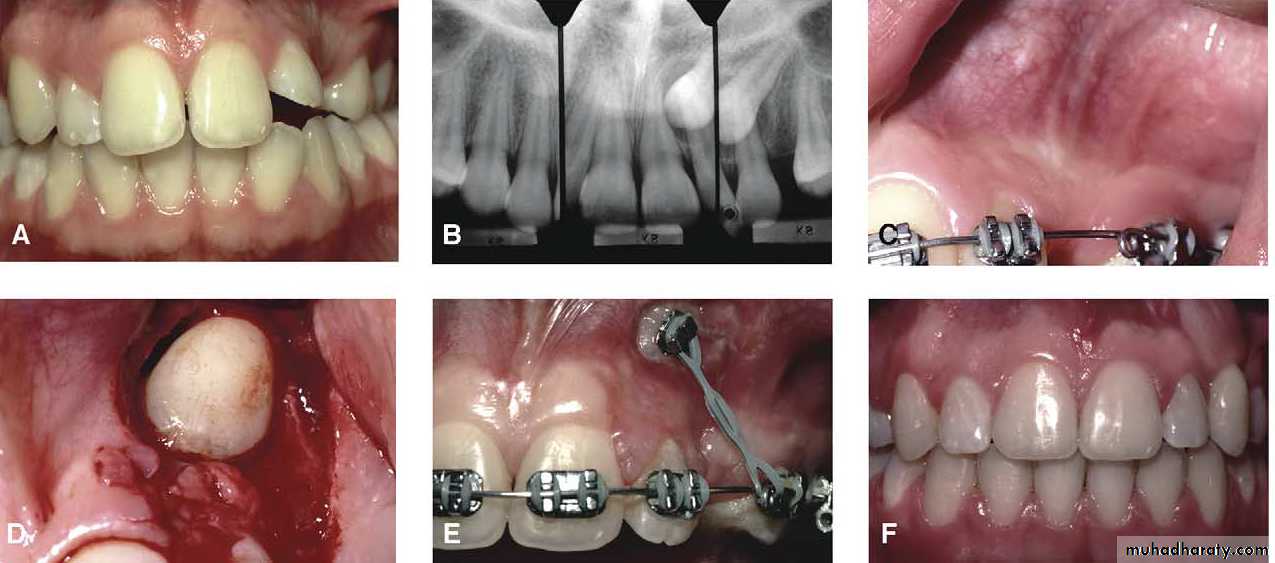

Surgical exposure with orthodontic treatment (palatal approach )

impaction